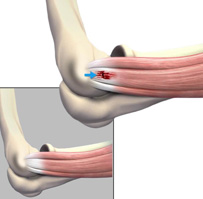

Tennis elbow is a common name for the elbow condition lateral epicondylitis.

Epicondylitis

Epicondylitis is an inflammation of the tendons surrounding the epicondyle, which is the bony protuberance in the elbow.